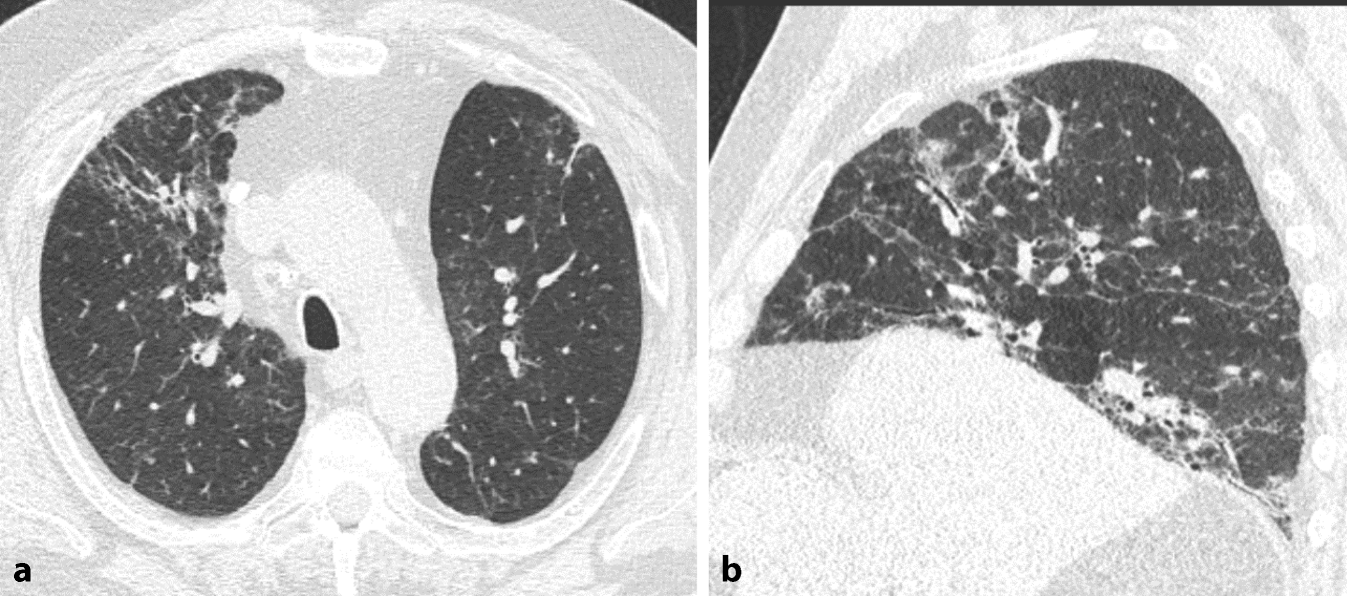

Abb. 4

Fibrotische exogen-allergische Alveolitis (EAA) mit viel Inflammation. a Axiale und b sagittale multiplanare Reformation (MPR) einer nativen High-Resolution-Computertomographie (HRCT). Oberlappenbetonte Fibrose erkenntlich an irreguläre Retikulationen und Traktionsbronchiektasen. Zudem diffus verteiltes Milchglas und Air-Trapping. Beachte auch das Drei-Dichte-Zeichen